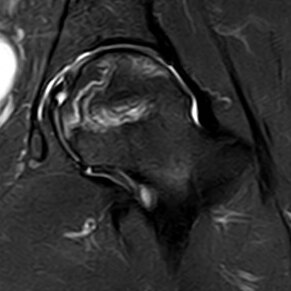

在股骨头坏死磁共振检查中,“双线征”是一个经常被提到的名词。

大多数学者公认“双线征”是股骨头坏死较为特异的征象。

“双线征”(double-line sign)是影像学名词,1987年Mitchell等这样描述:在T2WI SE或压脂序列,包围骨坏死灶的低信号带内侧出现高信号带,被认为是活骨与死骨反应界面,即低信号带代表硬化骨,高信号带代表充血和炎症内肉芽组织增生。

下图展示肉芽带和硬化带:

肉芽带与硬化带及其他

“双线征”出现率达80%,它只是坏死的特点而已,也有学者认为“双线征”也可能是“化学位移伪影”之故。

这就是典型的双线征:

内高外低的双线征

这样的是“ 三线征 ”: